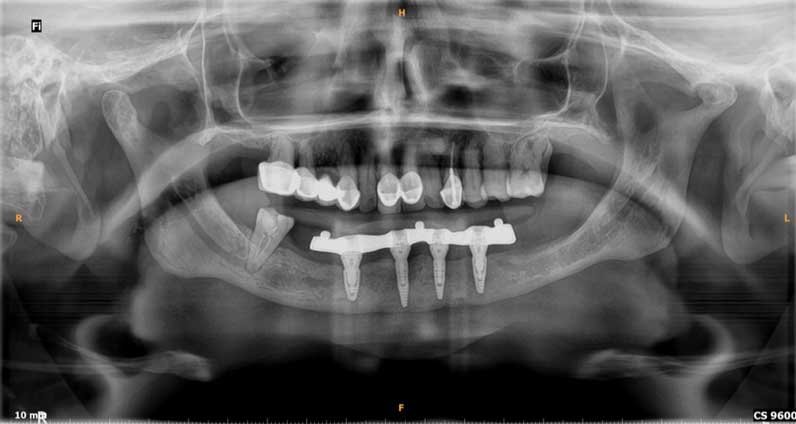

Patient ‘Monica Chawla‘ came to us at Indiadens dental clinic in South Delhi, unable to eat properly for a long time. Dr. Ujjwal Gulati rehabilitated her with implant-supported teeth, giving her a new lease on life. Now, she’s happily eating the foods she loves and is thrilled with her new, confident smile.